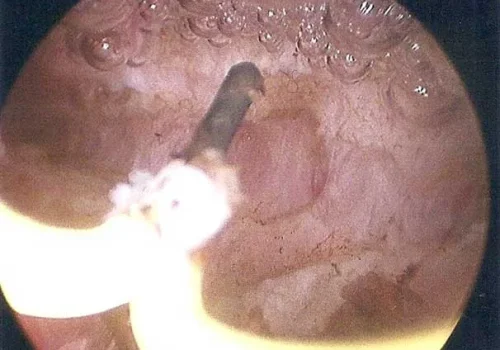

A Hysteroscopy with Division of Uterine Septum was performed.